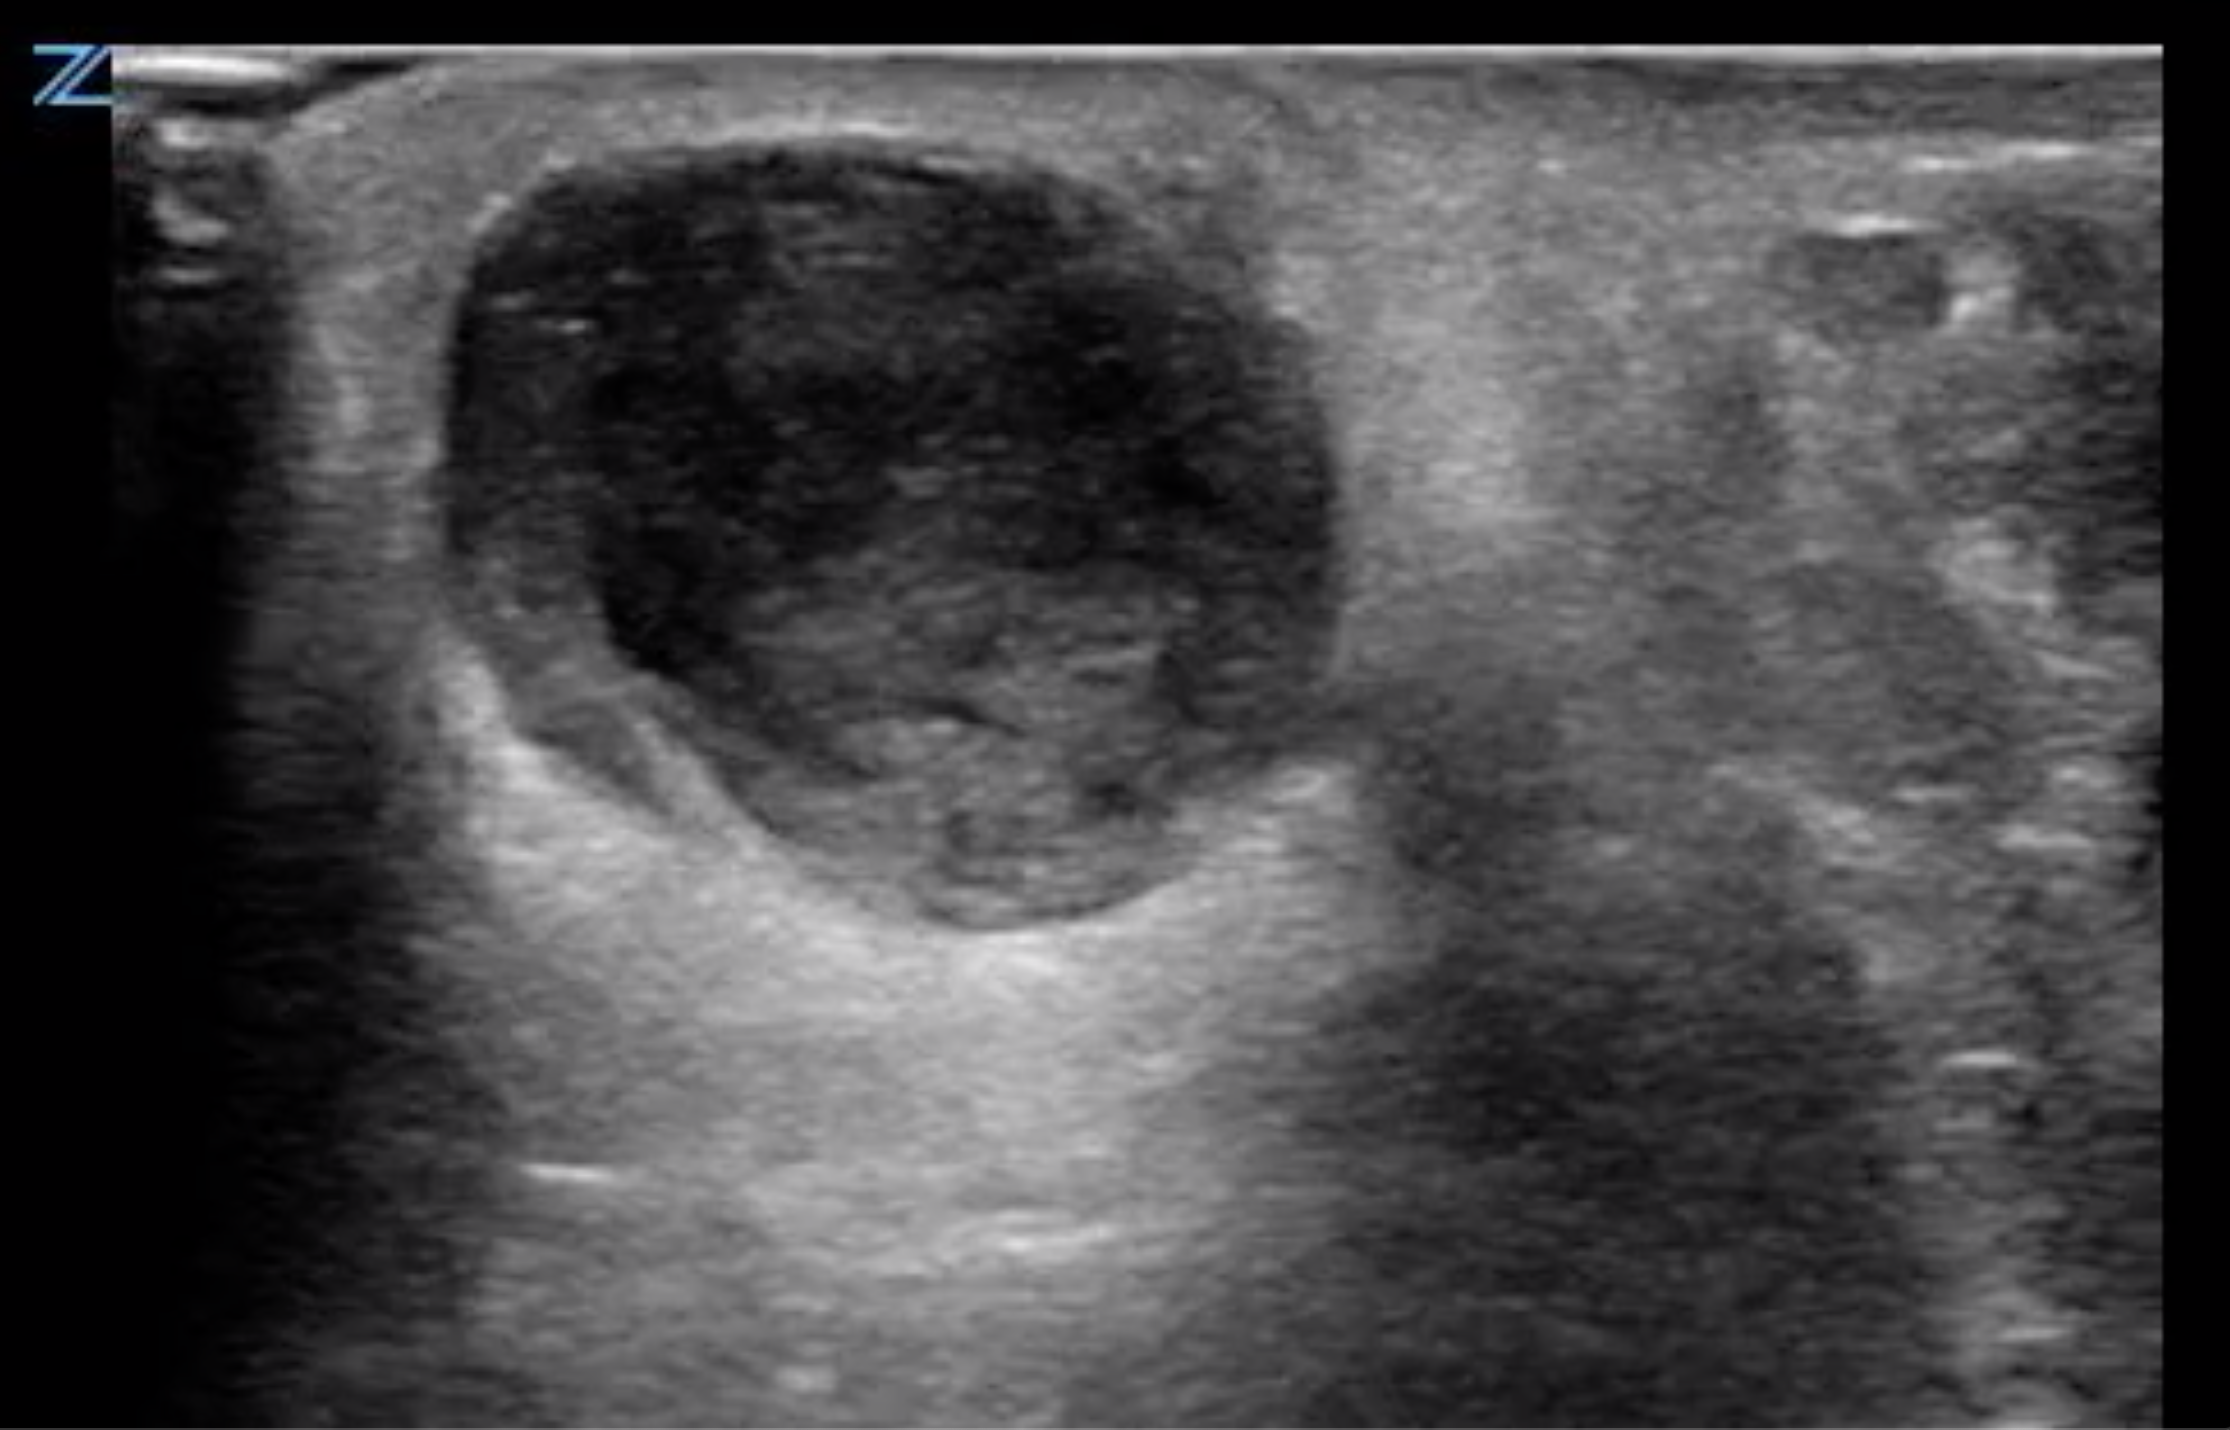

- Figure 2. Abscess containing hyperechoic debris

- On ultrasound, an abscess is a spherical or oblong structure that is largely anechoic or hypoechoic.

- However, as opposed to a simple cyst that will be uniformly anechoic throughout, an abscess will contain hyperechoic debris. This feature can be used to differentiate an abscess from a cyst.

- The walls of the abscess cavity might be distinct and hyperechoic, or they might have a ragged appearance and intermix with the adjacent tissue. Because of the anechoic nature of the abscess, posterior acoustic enhancement might be seen.

- Dynamic scanning, achieved with gentle compression of the probe, might cause the contents of the abscess to swirl, which can be diagnostic of an abscess.